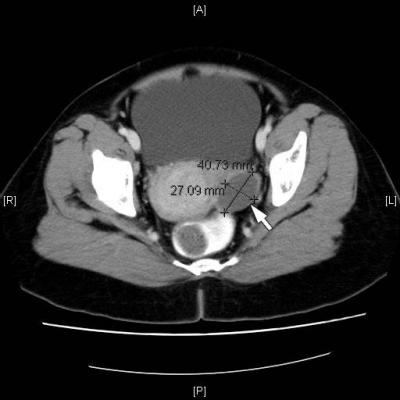

Figure.1: CT scan shows a cystic mass in the left adnexa (white arrow).